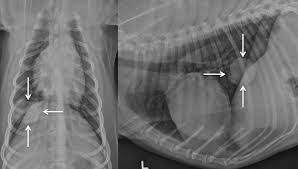

Secondary Lung Tumors In Dogs / Primary Lung Neoplasia Tumor A Veterinarian S Perspective - There are two type of lung cancer diagnosed in dogs.. This tumor tends to grow as a large, single, and solitary mass, but may spread within the lungs, to local lymph nodes, or even bone. Dogs with metastatic lung cancers generally have several tumors in the lungs, not just a single growth. In this article we will help you understand the diagnosis of cancer in dogs. Metastatic lung cancers (cancers that spread to the lungs from other locations) are much more common in dogs than primary lung cancers. Metastatic lung cancer originates in other parts of the body such as a leg bone, the mouth, or the thyroid gland, but has spread to the lung through the bloodstream.

Lung cancer accounts for about one percent of all cancers in dogs. Also called pulmonary tumors they have been classified into bronchogenic, bronchial gland, or bronchioalveolar according to the site of their location. Pulmonary carcinomas have a high tendency to metastasize, so full. Metastatic tumors in dogs are made up of cells of the original tumor, not the site in which they have moved to. Primary lung sarcomas and adenomas are rare in both species. This tumor tends to grow as a large, single, and solitary mass, but may spread within the lungs, to local lymph nodes, or even bone. Usually there are no symptoms in the early stages of canine lung cancer. Not only is it difficult to hear the words, but many owners struggle with understanding the process of their disease and when it's actually time to let them go. Your dog's tumor probably originated in his bones as osteosarcoma, in his mouth as oral melanoma, or in the blood vessels as hemangiosarcoma. However, primary lung cancers are being seen more frequently over the last 20 years. Dogs with metastatic lung cancers generally have several tumors in the lungs, not just a single growth. The lungs are a place that cancers tend to spread to more rapidly than other parts of the body. This is known as metastasis, and it is a secondary type of cancer in dogs.

There are chances though that the percentage may be higher, studies say. + types of lung tumors. Primary lung tumors are those that arise from the lungs, mostly from cells lining the bronchi. The lungs are a common site to which other types of cancer spread, such as with dogs diagnosed with bone cancer. The lungs are a place that cancers tend to spread to more rapidly than other parts of the body. Average age of dogs with primary lung tumors has been found. The american veterinary medical association (avma) reports that one in four dogs will develop cancer at some time in their life and that 50% of pets over the age of 10 will develop cancer. Pulmonary metastatic disease most commonly. Metastatic lung tumors are tumors originating from a cancer elsewhere in the body which has spread to the pet's lungs. Also called pulmonary tumors they have been classified into bronchogenic, bronchial gland, or bronchioalveolar according to the site of their location. In this article we will help you understand the diagnosis of cancer in dogs. The main highways of travel for cancer cells are the bloodstream and the lymphatic system (lymph nodes). Alveolar pattern observed in metastatic mammary and pulmonary neoplasia is due to confluence of smaller tumor nodules, hemorrhagic or necrotic reaction of lung parenchyma to tumor emboli, pulmonary edema secondary to airway obstruction by tumor, or extension of tumor into alveolar spaces + dogs.

Pulmonary Tumors The National Canine Cancer Foundation from wearethecure.org The most common causes of lung cancer in dogs includes: Secondary metastasis to the lungs is more common than primary canine neoplasm. Of the primary lung tumors in dogs and cats, ≥80% are malignant. The following diagnostics are recommended: In this article we will help you understand the diagnosis of cancer in dogs. Symptoms of lung metastases pulmonary metastases may not produce symptoms. The second kind of lung cancer in dogs is called metastatic lung cancer, which means the cancer originated somewhere else in the body, but has spread to the lung. Primary lung tumors are those that arise from the lungs, mostly from cells lining the bronchi.

The lungs are a place that cancers tend to spread to more rapidly than other parts of the body. The american veterinary medical association (avma) reports that one in four dogs will develop cancer at some time in their life and that 50% of pets over the age of 10 will develop cancer. Lung cancer in dogs may be primary, originating in the lungs or it may come from a different area of the body such as the liver, and then the cancer metastizes to the lungs.primary lung cancer in dogs is rare and has four stages, and it is important to detect the condition as early as possible, to be able to administer treatment that may save your dog's life. Other lung tumors in dogs may include a primary lung histiocytic sarcoma. The average age of dogs with primary lung tumors is approximately 11 years and the risk of developing lung cancer rises after the age of 13. Also called pulmonary tumors they have been classified into bronchogenic, bronchial gland, or bronchioalveolar according to the site of their location. Certain breeds are more predisposed to develop pulmonary tumors than others. When to euthanize a dog with cancer. Pulmonary metastatic disease most commonly. Metastatic lung cancer originates in other parts of the body such as a leg bone, the mouth, or the thyroid gland, but has spread to the lung through the bloodstream. Most often, tumors found in the lungs are secondary tumors (metastases). The second type is metastatic lung cancer whichis cancer that originates elsewhere in the body such as a leg bone, the mouth, or the thyroid gland, but has spread to the lung via the bloodstream. Adenocarcinoma and alveolar carcinoma are the most common types.